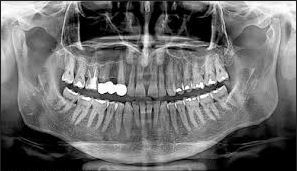

Ψηφιακή Πανοραμική Ακτινογραφία

Η πανοραμική είναι μια απλή δισδιάστατη εξέταση που παράγει μια ολοκληρωμένη απεικόνιση των δοντιών και των γνάθων. Ζητείται πολύ συχνά για μία αρχική εξέταση των δοντιών και της στοματογναθικής περιοχής γιατί παρέχει μιας υψηλής ποιότητας αρχική εικόνα της κατάστασης του στόματος των ασθενών.